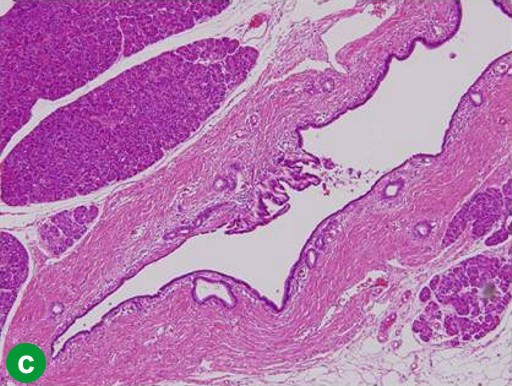

A 67-year-old man showed a pancreatic tumor on abdominal US at an annual medical checkup. An abdominal CT scan detected a 1 cm tumor in the body of the pancreas and main pancreatic duct dilatation of the distal pancreas (Figure 3a). A distal pancreatectomy with splenectomy was performed in February 2006. Histopathological examination confirmed a well-differentiated adenocarcinoma with no vessel or lymph duct invasion and no lymph node metastasis (Figure 3b). Mild atypical epithelia were observed at the cut edge of the main pancreatic duct (T1N0M0; R0; pathological stage: IA) (Figure 3c). Periodic checkups without adjuvant chemotherapy were carried out for 2 years, and there were no abnormal findings in abdominal CT scans or tumor marker assays.

|

Figure 3. Case#2: initial operation. a. A tumor approximately 1 cm in diameter and main pancreatic duct dilatation of the distal pancreas was detected in the pancreatic body on abdominal CT. b. Adenocarcinoma of the pancreas. Atypical cells with a swollen nucleus formed a papillary projection. c. Mild atypical epithelia projected from the cut edge of the main pancreatic duct. (H&E stain, x100). |